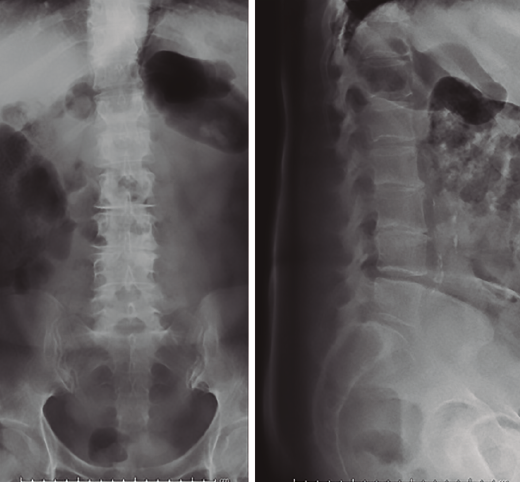

Figura 1. Radiografías iniciales con severa discopatía L2/L3 y discopatía L3/L4.

Se realizó analítica completa: hemograma normal, marcadores proteína C reactiva (PCR) y velocidad de sedimentación globular (VSG) claramente elevados, 80 y 63 respectivamente, Rx y RM (Figuras 1 a 4).

Figura 3. Radiografías al ingreso en nuestra unidad. Seis semanas respecto a las iniciales. Destrucción completa disco L2/L3.